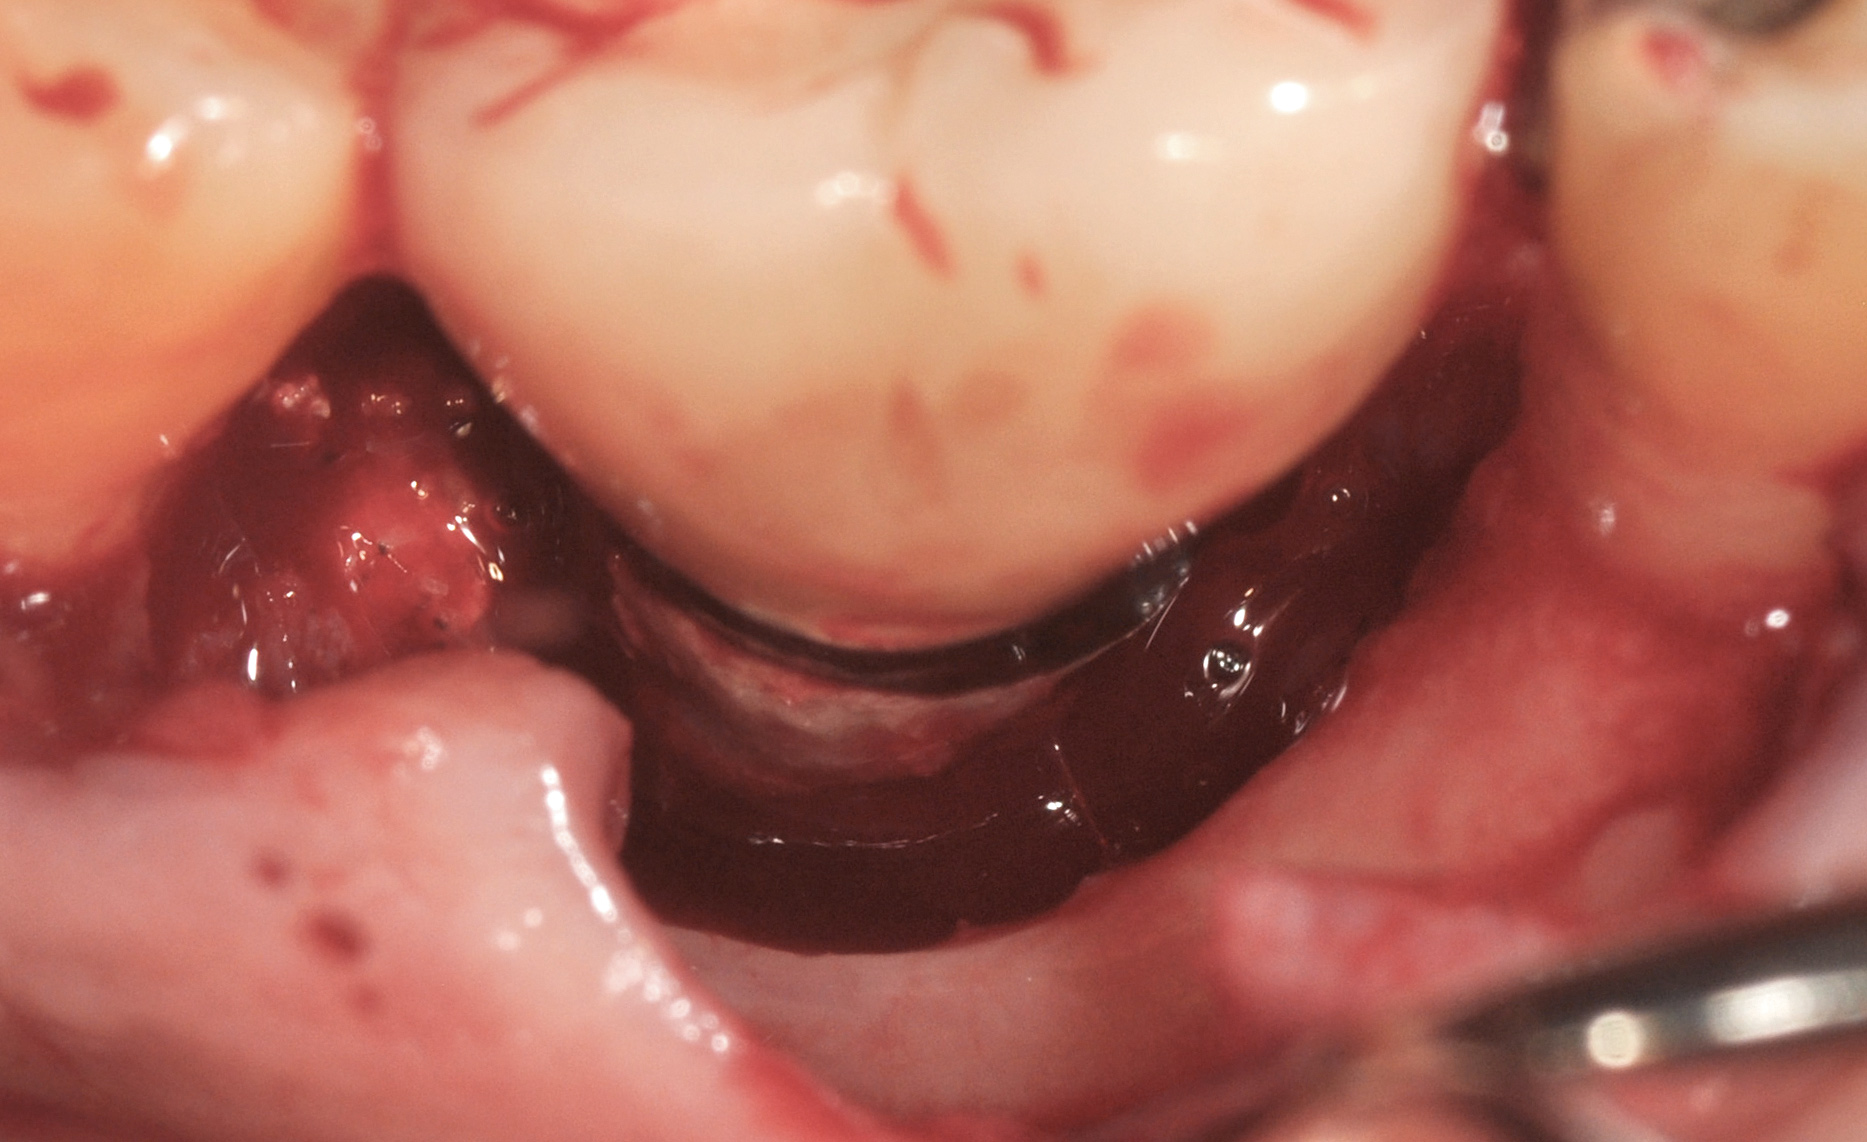

A surgical flap procedure was performed with the intent of thoroughly debriding the granulomatous tissue from the osseous defect (Figure 18 and Figure 19), mechanically and chemically detoxifying the surface of the implant (Figure 20 through Figure 22), and grafting the infrabony component of lesion with bone xenograft (Bio-Oss®, Geistlich Pharma, www.geistlich-na.com) in an attempt to reduce the vertical defect (Figure 23). To concurrently resolve the mucogingival problem, the plan called for placing a dermal allograft (Dermis Allograft, DENTSPLY International, www.dentsply.com) on the buccal (Figure 24) and then replacing the flap (Figure 25).

Fig 22. Copious irrigation with dilute hydrogen peroxide was used to chemically detoxify the surface of the implant and the bony defect.

Fig 23. Fill of the infrabony defect with bone xenograft.